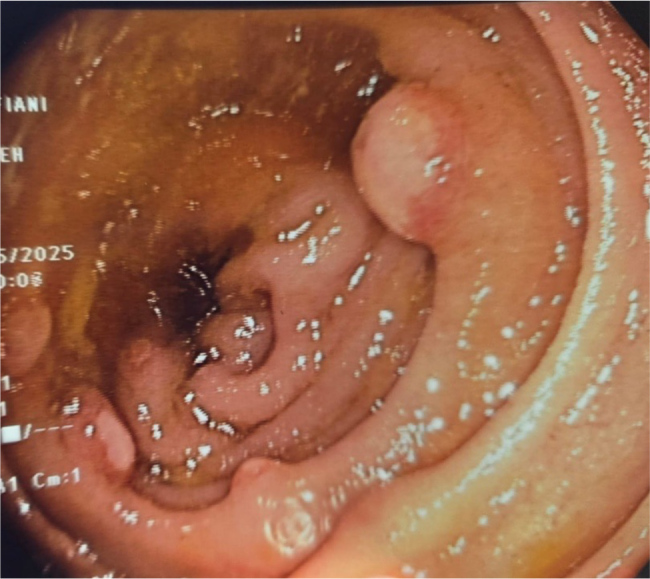

Blind loop syndrome is a malabsorptive condition resulting from intestinal stasis, which promotes bacterial overgrowth and leads to various gastrointestinal and systemic manifestations. It often occurs secondary to anatomical or motility abnormalities, particularly after gastrointestinal surgeries. We present the case of a 75-year-old male with a history of colon cancer status post right hemicolectomy with ileo-colonic anastomosis, who was incidentally found to have severe iron deficiency anaemia during a routine check-up. One year prior, follow-up endoscopies were normal. However, recent investigations revealed a hyperplastic polyp in the gastric cardia and, more importantly, a blind loop with ulcerations distal to the ileum on colonoscopy. Biopsies confirmed ulcerated ileal/colonic mucosa with granulation tissue. The patient underwent surgical resection of the blind loop with the creation of an ileo-transverse anastomosis. Postoperatively, he recovered well and was discharged on a regular diet. This case illustrates the importance of considering blind loop syndrome in patients with a history of bowel surgery who present with non-specific symptoms such as anaemia. It also highlights the potential for delayed onset and the diagnostic value of endoscopy when routine workups are inconclusive. Surgical correction remains the definitive treatment in anatomically driven cases, offering significant symptomatic relief and prevention of further complications.

Learning points: Blind loop syndrome should be suspected in patients with prior bowel surgeries.It can present as anaemia.It may present years after surgery.It may be more common than statistics suggest, as it is often underdiagnosed or misdiagnosed.